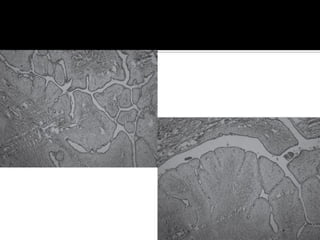

 El término Phyllodes (forma de hoja) se debe

a las proyecciones papilares (al microscopio).

 Microscópicamente se caracteriza por:

- Proyecciones papilares del estromal.

- Intercalando zonas de hiperplasia y atipia.

 El componente estromal, diferencia de FAM,

y formas benignas de malignas.

 Componente epitelial distorsionado por el

predominio y la prominencia del estroma.

 Comprime los conductos y da lugar a

hendiduras y a espacios quísticos tapizados

por epitelio.